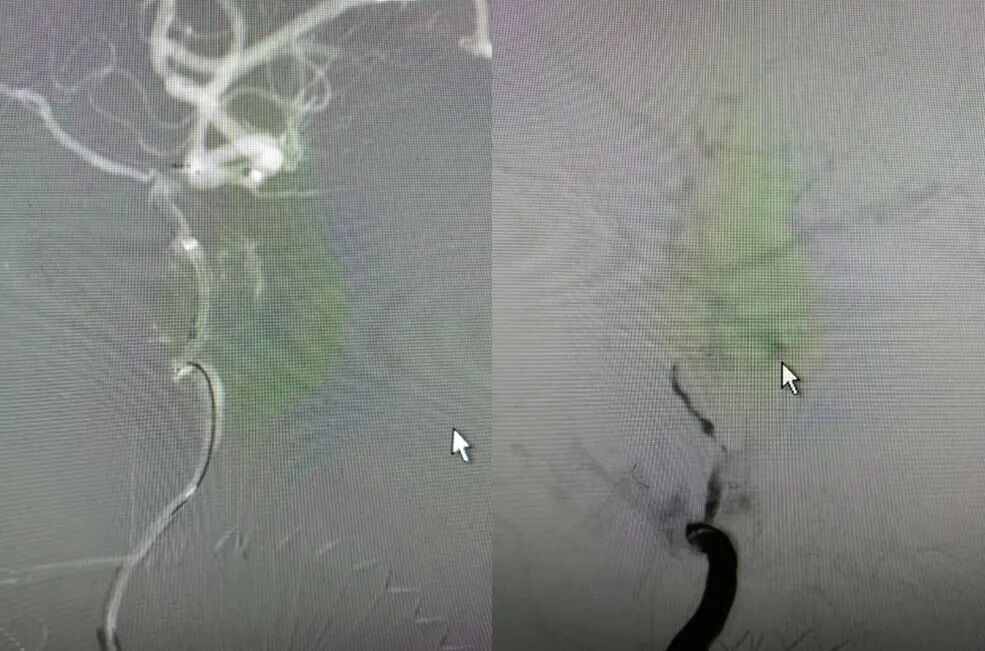

6F-远端通路导管在黑泥鳅导丝的指引下通过闭塞段送至眼动脉段,造影证实闭塞段在海绵窦段,予以ADPAT技术取出少量血栓,仍未开通。

通过微导管释放取栓支架,SWIM取栓技术,可见海绵窦段狭窄,前向血流不稳定。

利用PTA球囊导管对狭窄处进行扩张,可见狭窄明显改善,但眼动脉段以后闭塞,再次将取栓支架予以取栓,可见斑块逃逸至M1段。

多次利用取栓支架SWIM技术对逃逸斑块进行取栓但未成功。

利用赛诺神畅 NOVA DES®内药物洗脱支架锚定后释放,血管再通,mTICI 3级,局部动脉给药替罗非班(0.2ug/kg.min)约3ml,持续15分钟。静脉(0.1ug/kg.min)持续泵入24小时后改为口服双抗。